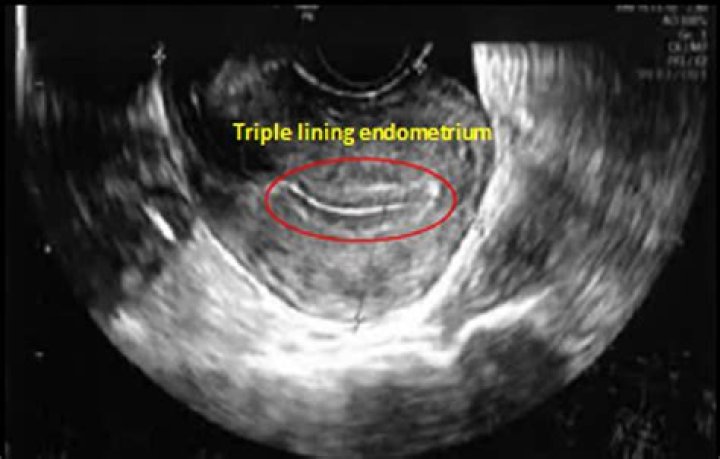

Does uterine lining regenerate?

A: Every menstrual cycle and for >400 such cycles in a woman's reproductive life span, the uterus sheds its inner lining to a thickness of ~4-10 mm and is completely regenerated back within a week. The process has both evolutionary as well as physiological significance.